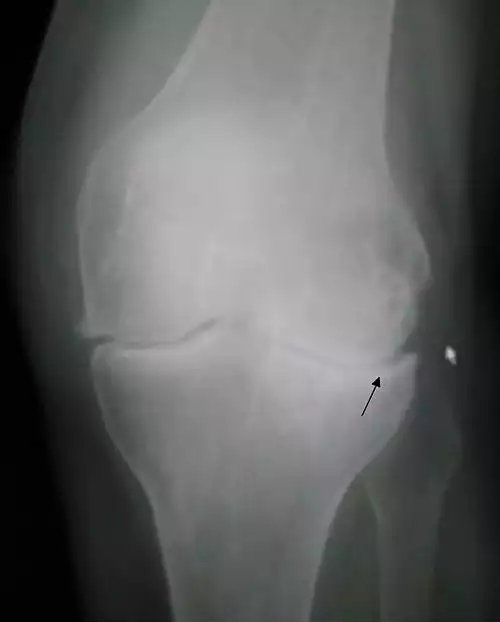

در آرتروز تحلیل غضروف مفصلی و درگیری استخوان زیر غضروفی داریم که باعث التهاب بافت های اطراف می گردد. این عارضه ممکن است هر یک از مفاصل را درگیر سازد، ولی شایع ترین مفاصل درگیر عبارتند از مفاصل دست، پا، زانو، ران و ستون فقرات. این بیماری بسیار شایع است و در ۲۵٪ ویزیت های پزشکان عمومی و ۸۰٪ رادیوگرافی افراد بالای ۶۵ سال دیده می شود؛ ( البته فقط ۷۰٪ آنان علامت دارند ).

آرتروز بیماری مَفصلی است که ابتدا غضروف مفصل را درگیر می نماید. غضروف بافتی لغزنده است که انتهاهای استخوان ها را در یک مفصل می پوشاند. استخوان ها داشتن حرکتی آسان بر روی یکدیگر را مدیون غضروف های سالم هستند. وظیفه دیگر غضروف ها جذب تکانه ها در طی حرکات فیزیکی می باشد. در بیماری آرتروز غضروف ها نازک شده و به تدریج در برخی نواحی از بین می رود که باعث می شود، استخوان های زیر غضروف ها به همدیگر ساییده شوند. نهایتاً درد، التهاب آواست و کاهش حرکت در مفصل به وجود آید. به مرور زمان مفصل شکل طبیعی خودش را از دست می دهد و زوائدی استخوانی در لبه های آن ایجاد می گردد که خود باعث درد و ناراحتی بیشتر می شود. برعکس سایر التهاب های مفصلی مانند روماتیسم مفصلی، آرتروز تنها مفاصل را درگیر می نماید و به سایر اندام ها کاری ندارد. روماتیسم مفصلی افراد جوان تر را مبتلا می کند و ممکن است علاوه بر درگیری مفصل فرد احساس مریضی، خستگی یا تب نماید.